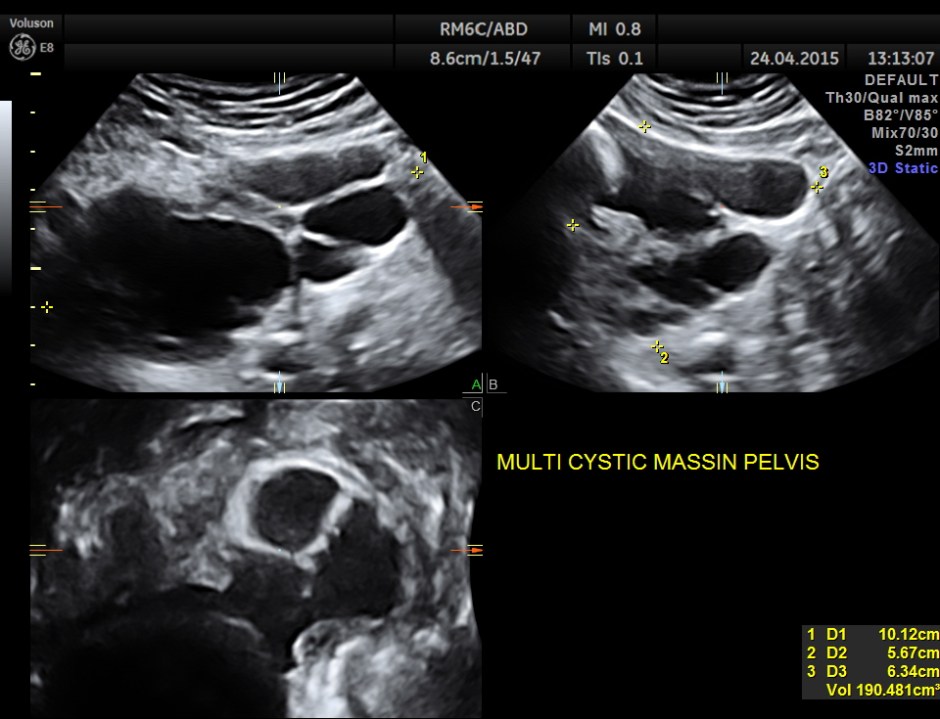

Superior angling shows a multi cystic pelvic mass – ? bladder diverticulae

CT scan confirmed the ultrasound findings :

LARGE CALCULUS IN THE URINARY BLADDER WITH MULTIPLE DIVERTICULAE IN THE BLADDER “